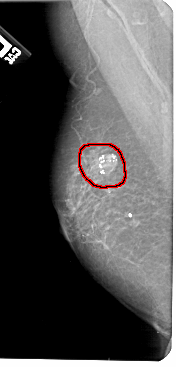

A_1306_1.LEFT_MLO

FILE: A_1306_1.LEFT_MLO.OVERLAY

TOTAL_ABNORMALITIES 1

ABNORMALITY 1

LESION_TYPE CALCIFICATION TYPE AMORPHOUS DISTRIBUTION N/A

LESION_TYPE MASS SHAPE OVAL MARGINS CIRCUMSCRIBED

ASSESSMENT 2

SUBTLETY 5

PATHOLOGY BENIGN

TOTAL_OUTLINES 1

BOUNDARY